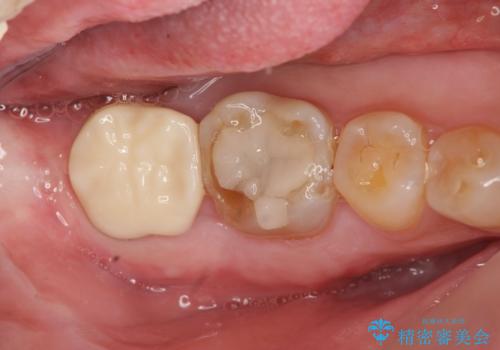

歯ぎしりによる異常に低い歯冠高径 歯周外科による解決

- 右下修復物の破損修復を希望され来院されました。

失活歯であるため根管治療ののちクラウン製作が治療計画として考えられますが長年のすり減りによりクラウン高径がほとんどなくてなってしまっている状態です。

歯周外科を行い歯茎の位置を下げることで安定したクラウン製作ができる状態を目指します。

あまりにもクラウン高径が低いと、安定性が悪くなりセメントの溢出を招き虫歯の再発リスクを高めます。